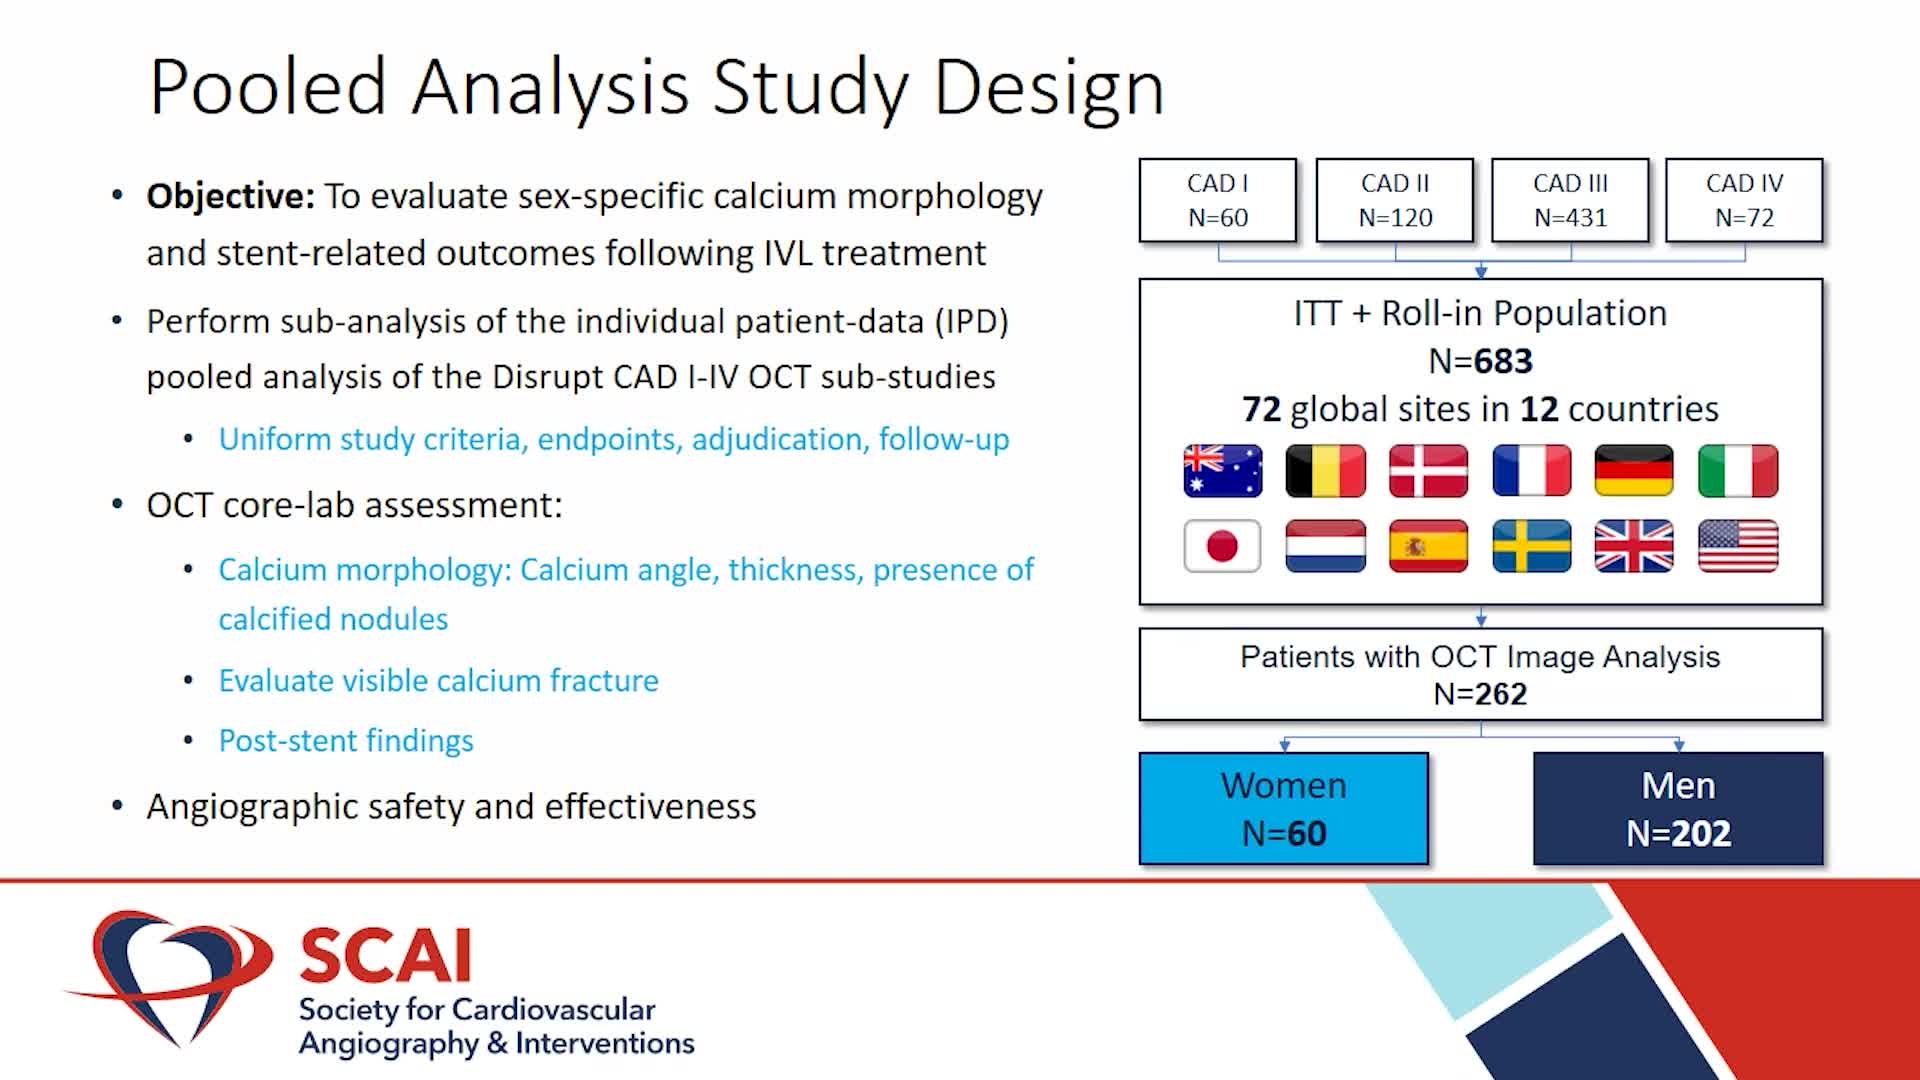

Intravascular Lithotripsy for Treatment of Severely Calcified Coronary Artery Disease: The Disrupt CAD III Study